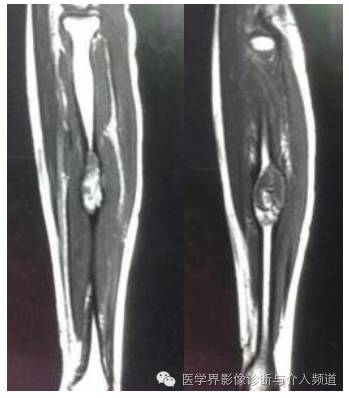

MR增强

CT:病变多呈囊状膨胀性骨破坏,骨壳菲薄,破坏区内一般可见多发含液囊腔,有的可见液液平面,囊腔间隔为软组织密度影,并可见钙化或骨化。增强囊间隔强化而显示清晰。

MR:一般呈多囊状改变,37%-87.5%的病例囊内有液液平面,在扫描前保持不动10分钟较容易显示。T2WI上液平面上层一般为高信号,可能为血清液或高铁血红蛋白;下层为低信号,可能是细胞及碎裂细胞产物。